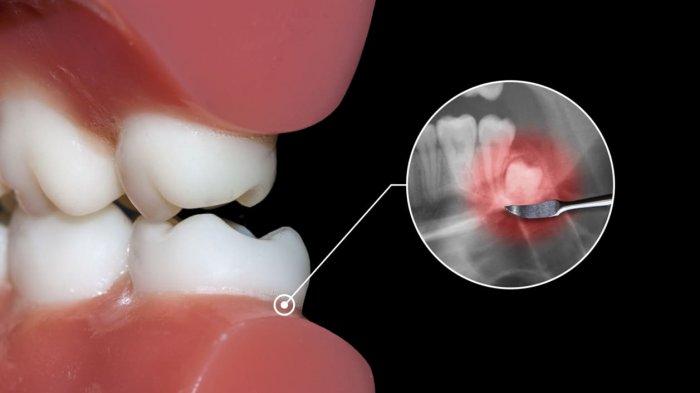

Bila sejak awal posisi gigi bungsu tidak baik, tentunya untuk memperbaiki posisi tersebut akan sulit.

"Kalau ngebagusin posisinya sulit ya. Karena biasanya tumbuh gigi kalau baru benih doang belum ada akar giginya, itu kita akan sangat sulit ya untuk menggerakkan. Biasanya memang ditunggu sampai tumbuh, sampai gigi bungsunya terlihat bentuknya. Lengkap ada akarnya gitu,"

Karena kebanyakan kasus sekarang, gigi bungsu tidak bisa tumbuh karena rahang kekurangan atau rahang sempit.

"Space nya gak ada, jadi gigi tumbuhnya cuma setengah. Itu yang bikin sakit. Itu kalau dibenerin juga gimana? Jadi lebih baik kita ambil," lanjutnya